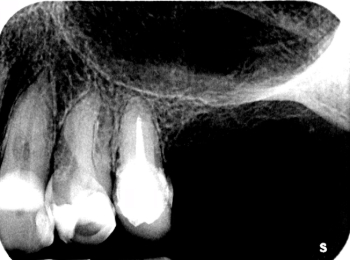

Röntgen Revision 25

Zustand nach Revision 25 und Extraktion 26 und 27.

Röntgen Ausheilung

Zustand nach Ausheilung 25 apikal nach Revision und Regio 26 und 27 nach Extraktion.